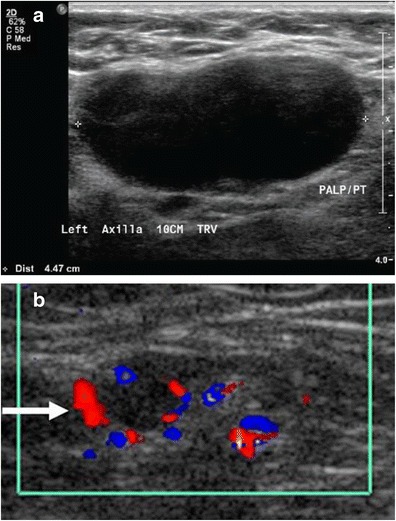

Large lymph nodes are referred to as lymphadenopathy (LAD).

Mantle cell lymphoma clinically presents with lymphadenopathy without pain that first appears in late adulthood.

Patients with Hodgkin lymphoma (HL) typically present with enlarged cervical or mediastinal lymph nodes.